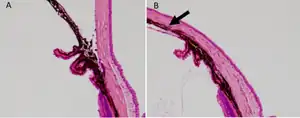

b) Anterior segment of laser-treated a) and control eye was histologically assessed. The arrow indicates the closed angle induced by laser photocoagulation. | |